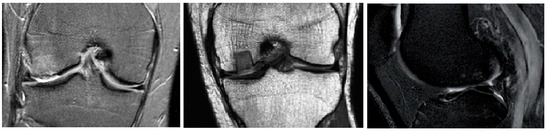

Novel Hybrid Optimized Clustering Schemes with Genetic Algorithm and PSO for Segmentation and Classification of Articular Cartilage Loss from MR Images

by Jan Kubicek, Alice Varysova, Martin Cerny, Jiri Skandera, David Oczka, Martin Augustynek and Marek Penhaker

Mathematics 2023, 11(4), 1027; https://doi.org/10.3390/math11041027 - 17 Feb 2023

Cited by 4 | Viewed by 2424

Abstract

Medical image segmentation plays an indispensable role in the identification of articular cartilage, tibial and femoral bones from magnetic resonance imaging (MRI). There are various image segmentation strategies that can be used to identify the knee structures of interest. Among the most popular [...] Read more.

Medical image segmentation plays an indispensable role in the identification of articular cartilage, tibial and femoral bones from magnetic resonance imaging (MRI). There are various image segmentation strategies that can be used to identify the knee structures of interest. Among the most popular are the methods based on non-hierarchical clustering, including the algorithms K-means and fuzzy C-means (FCM). Although these algorithms have been used in many studies for regional image segmentation, they have two essential drawbacks that limit their performance and accuracy of segmentation. Firstly, they rely on a precise selection of initial centroids, which is usually conducted randomly, and secondly, these algorithms are sensitive enough to image noise and artifacts, which may deteriorate the segmentation performance. Based on such limitations, we propose, in this study, two novel alternative metaheuristic hybrid schemes: non-hierarchical clustering, driven by a genetic algorithm, and Particle Swarm Optimization (PSO) with fitness function, which utilizes Kapur’s entropy and statistical variance. The goal of these optimization elements is to find the optimal distribution of centroids for the knee MR image segmentation model. As a part of this study, we provide comprehensive testing of the robustness of these novel segmentation algorithms upon the image noise generators. This includes Gaussian, Speckle, and impulsive Salt and Pepper noise with dynamic noise to objectively report the robustness of the proposed segmentation strategies in contrast with conventional K-means and FCM. This study reveals practical applications of the proposed algorithms for articular cartilage extraction and the consequent classification performance of early osteoarthritis based on segmentation models and convolutional neural networks (CNN). Here, we provide a comparative analysis of GoogLeNet and ResNet 18 with various hyperparameter settings, where we achieved 99.92% accuracy for the best classification configuration for early cartilage loss recognition. Full article

Show Figures

Figure 1